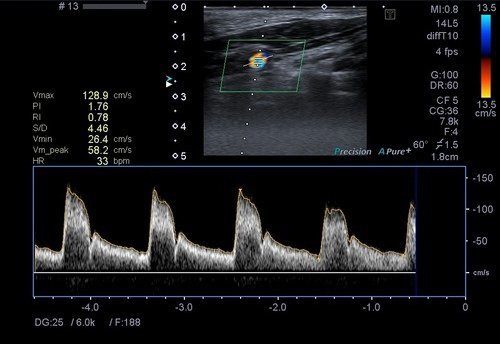

Karotis renkli doppler ultrason ile karotis damarımız (şah damarı) değerlendirilir. Bu damarda olası darlıklar, tıkanıklıklar, plaklar, balonlaşmalar (anevrizma) ve akım hızları-volümleri değerlendirilir. Bu damarlardaki problemler, beyni besleyen ana damarlar olduklarından hayati önem arz etmektedir.

Bu damarlarda tıkanıklıklar, balonlaşmalar (anevrizma), daralmalar ve akım hızları-volümleri değerlendirilir. Vertebral arterlerin oluşturduğu toplam debi yeterli düzeyin altında ise hastada vertigo oluşumuna sebep olabilir.